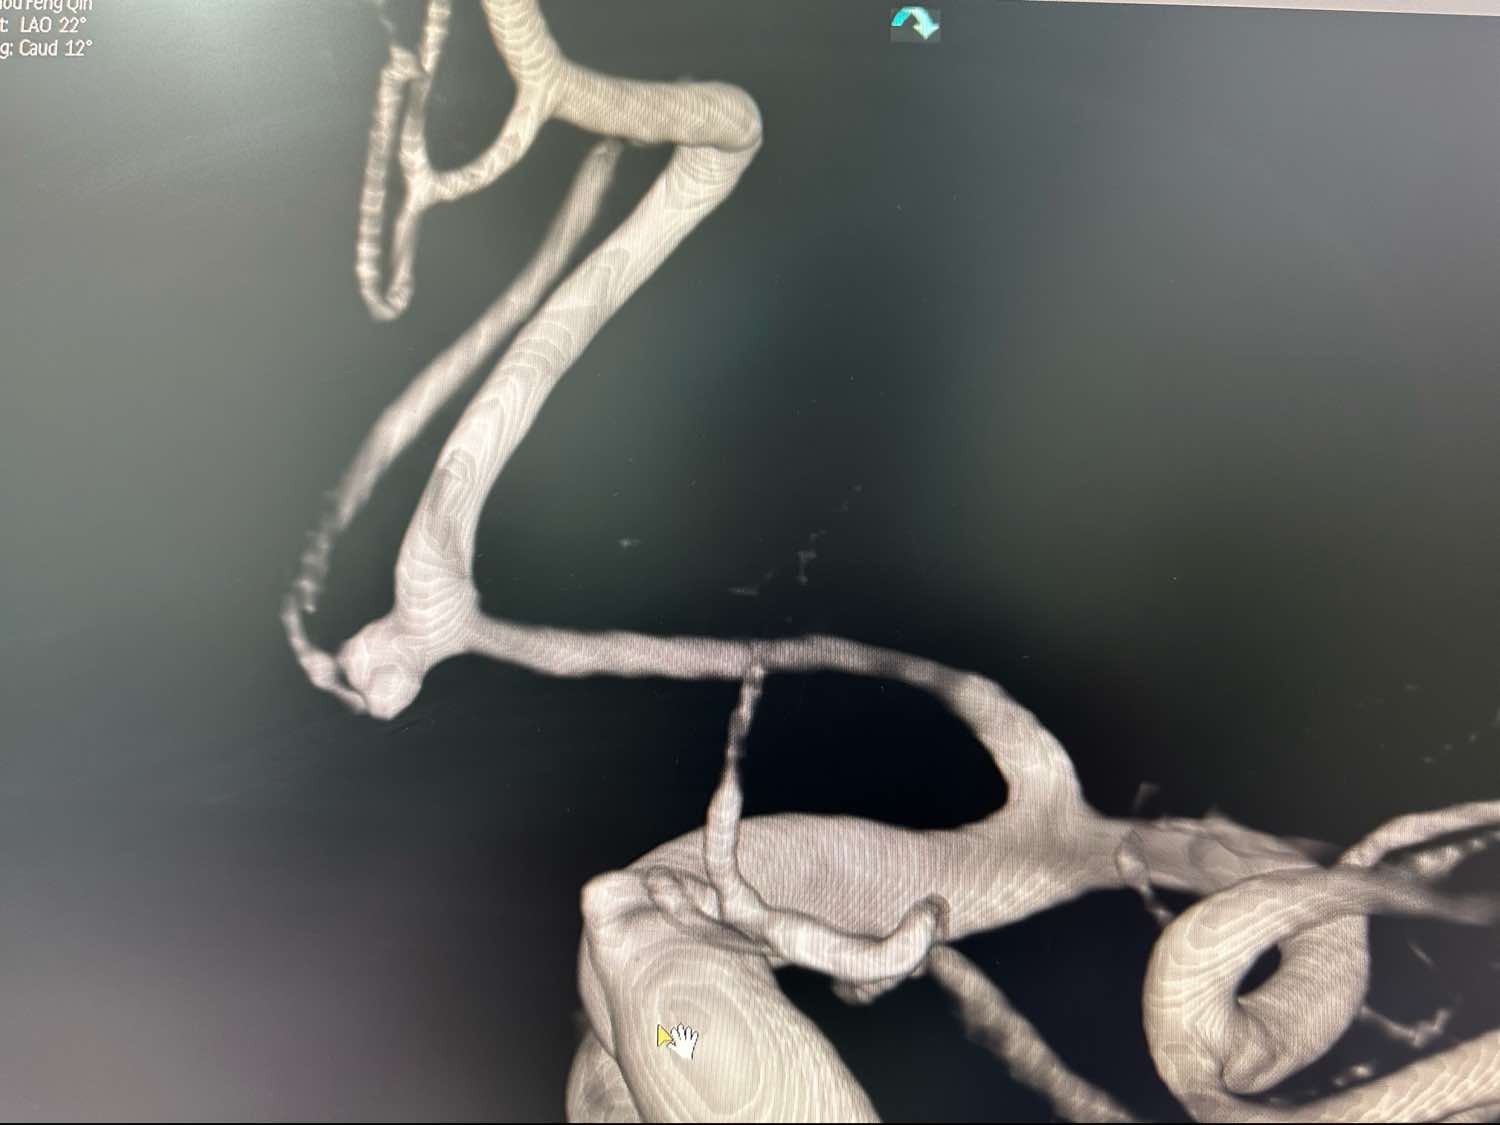

另外一个角度